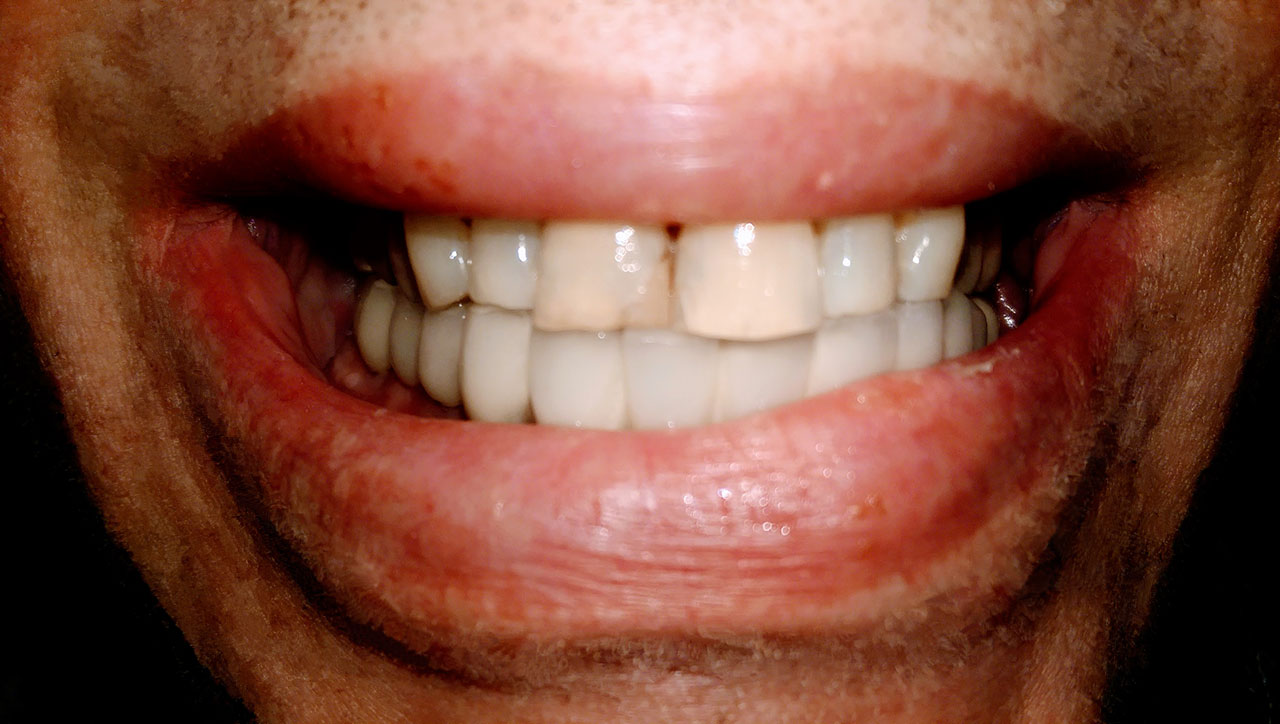

Elhanyagolt fogsor cseréje 2 nap alatt

2 nap alatt varázsoltuk ezt a szép esztétikus alsó, felső körhídat implantátumokkal megtámasztva a korábban elhanyagolt szájba. Az 1. nap 26 fogat távolítottunk el, mert annyira rossz állapotban voltak, és rögtön azonnal terhelhető IHDE svájci implantátumokat raktunk be, fentre 8, lentre 6 darabot. A sebeket összevarrtuk és intraorális szkennerrel digitális lenyomatot vettünk. 2 nap múlva pedig beragasztottuk a kész PMMA műanyag körhidakat. Dr. Kelemen Péter és a Symbion Fogtechnika munkája.